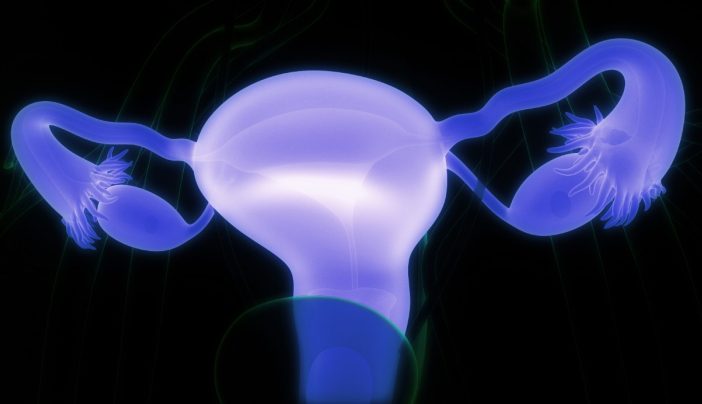

Ovarian cysts and cancer: is there a link?

Benign or noncancerous ovarian cysts are common in women of childbearing age. And most premenopausal women who have such symptoms at any given time probably don’t realize it.

but what that is Ovarian cyst? how are they treated? And do they increase your growth potential? ovarian cancer?

Simple ovarian cysts, also called functional cysts, are fluid-filled sacs that develop on or within the ovary as a normal part of the menstrual cycle. They appear and disappear based on hormonal fluctuations.

There are several different types such as:

- follicular: So named because it is located inside the follicle where the egg develops.

- corpus luteum: The name also derives from its location within a temporary structure that develops within an empty follicle after a mature egg has been released.

- “chocolate”: It is so called based on its appearance because it is filled with black matter such as blood. These include hemorrhagic cysts and sometimes ovarian endometriomas.

Simple ovarian cysts appear hollow, regardless of their name or location. scanultrasound shows clean borders and black interiors.